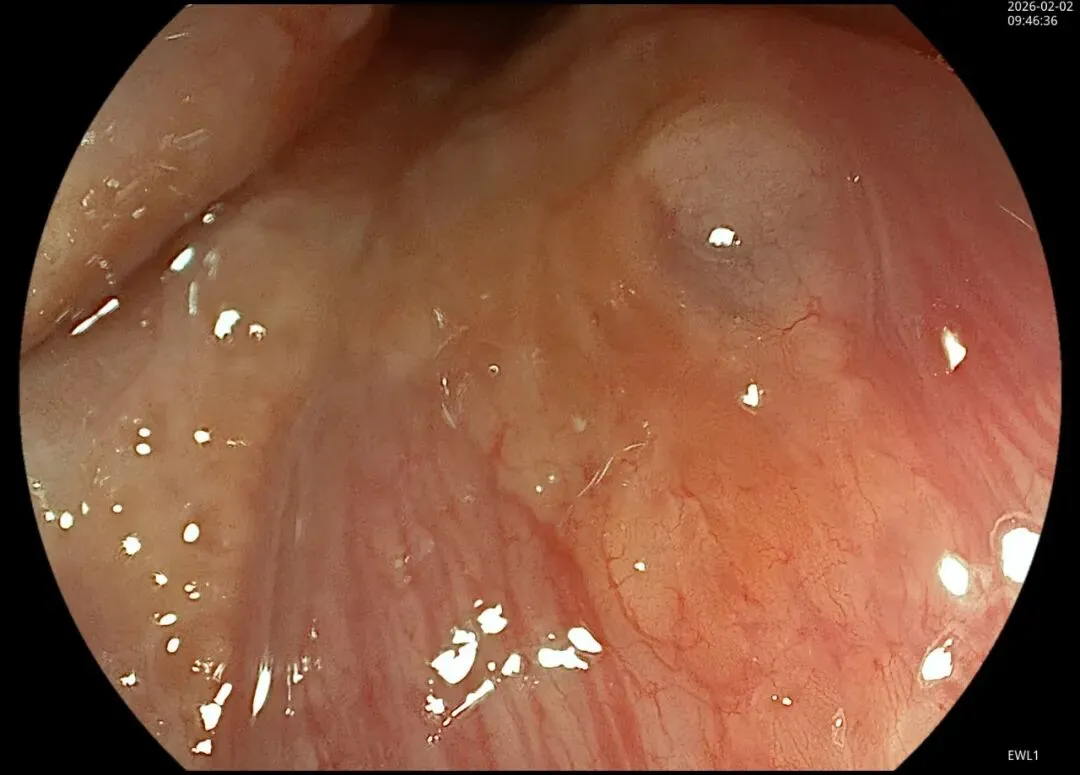

这一期不用码字,挺好的,很可惜一直没机会听过胡导讲的关于这个“花环征”的大课,学习内容来源于雨夜大师的号花环征:AIG背景的胃食管结合部的黄色颗粒状隆起及半透明“泡状”改变

补充自己在两例A型胃炎/AIG 观察到的“花环征”,巩固下学习效果。。。

1.白光表现为胃食管交界处黄色颗粒状隆起及半透明“泡状”改变

2.窄带光下可见颗粒状隆起呈褐色改变,放大可见细微网状血管结构及半透明“泡状”改变